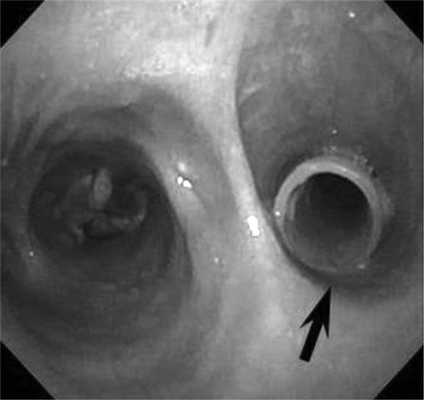

Пациент С., 28 лет, 29.07.14 был придавлен автомобилем к стене. Госпитализирован в ЦРБ г. Александрова, где при обследовании диагностирована тяжелая закрытая травма груди: множественные переломы ребер с двух сторон с разрывом легких, двусторонний пневмоторакс, правосторонний гемоторакс, подкожная эмфизема грудной клетки. Произведены правосторонняя торакотомия, ушивание разрывов верхней доли легкого, санация и дренирование правой плевральной полости, дренирование левой плевральной полости, диагностическая лапаротомия, ревизия органов брюшной полости. Через сутки (30.07.14) для дальнейшего лечения пациент переведен в НИИ СП им. Н.В. Склифосовского. При поступлении состояние больного тяжелое. Сознание - 10 баллов по шкале комы Глазго. Кожные покровы бледные, цианотичные. Искусственная вентиляция легких (ИВЛ) через оротрахеальную интубационную трубку. Грудная клетка равномерно участвовала в акте дыхания. Диагностирована двусторонняя подкожная эмфизема грудной клетки и шеи. Аускультативно дыхание жесткое, ослаблено с обеих сторон, больше справа. По дренажам из правой плевральной полости отмечено периодическое поступление воздуха. ЧСС 124 в минуту, АД 120/70 мм рт.ст. При рентгенологическом исследовании выявлена эмфизема мягких тканей грудной клетки с обеих сторон, переломы II-VII ребер справа и IV-VIII - слева, снижение прозрачности легочного поля в верхних и средних отделах правого легкого за счет контузионных изменений и кровоизлияний. При КТ-исследовании визуализированы множественные полисегментарные ушибы обоих легких с формированием гемопневматоцеле в нижней доле правого легкого, пневмомедиастинум, множественные переломы ребер и эмфизема мягких тканей передней грудной стенки. При фибробронхоскопии (ФБС) через интубационную трубку в просвете трахеобронхиального дерева, больше справа, выявлено значительное количество крови и сгустков. Выполнена санация просвета трахеи и бронхов раствором диоксидина 0,01% 60 мл. Сгустки крови удалены. В промежуточном бронхе визуализирован сгусток крови длиной 20-25 мм, занимающий 2/3 просвета бронха. По латеральной стенке бронха, не прикрытой сгустком крови, определялся дефект стенки бронха. При проведении аппарата дистальнее сгустка визуализировали среднедолевой и нижнедолевой бронхи. При ФБС, выполненной через 12 ч, в просвете бронхов определяли умеренное количество слизистого секрета с примесью крови. На 5 мм дистальнее карины по заднемедиальной стенке правого главного бронха выявлен дефект стенки 10 мм в диаметре с рваными краями и с образованием полости диаметром 10-15 мм (рис. 1). Правый верхнедолевой бронх не изменен, сегментарные бронхи проходимы. На расстоянии 10 мм от шпоры правого верхнедолевого бронха и на уровне верхнего края устья среднедолевого бронха визуализирован циркулярный разрыв стенки промежуточного бронха с диастазом краев 20-25 мм (рис. 2). Средне- и нижнедолевые бронхи правого легкого не изменены. Таким образом, локализация разрывов бронхов не позволяла исключить правостороннюю пневмонэктомию как возможный объем операции. Однако вмешательство с раздельной интубацией бронхов и выключением правого легкого на фоне массивной контузии левого легкого, выраженной легочной недостаточности и постгипоксического синдрома представлялось крайне рискованным. В связи с полным расправлением легких, отсутствием значительного сброса воздуха по дренажам из плевральной полости и нарастающей эмфиземой на фоне ИВЛ решено воздержаться от операции и выбрать консервативную тактику. Проводили комплексную интенсивную терапию: ежедневные двукратные санационные ФБС; антибиотикопрофилактика (цилапенем 4000 мг/сут в/в, метронидазол 1000 мг/сут в/в); переливание иммуноглобулина 100 мл в/в, 2 доз эритроцитной массы и 11 доз свежезамороженной плазмы крови, 100 мл/сут 10% альбумина; муколитическая, ингаляционная, противовоспалительная терапия. На 2-е сутки наложена трахеостома для продленной ИВЛ.

Рис. 1. Разрыв правого главного бронха. Дефект заднемедиальной стенки правого главного бронха 10 мм в диаметре с рваными краями и с образованием полости диаметром 10-15 мм (указано стрелкой).